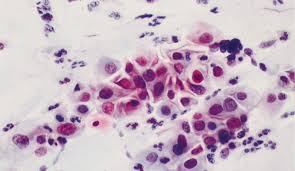

Cytology Zoom On Twitter High Grade Squamous Intraepithelial Lesion Hisl Note The Coarse Chromatin And Inconspicuous Nucleoli As Well As The Thickened Irregular Nuclear Outlines Nuclear To Cytoplasmic N C Are Almost 1 1 Cytology Zytologie